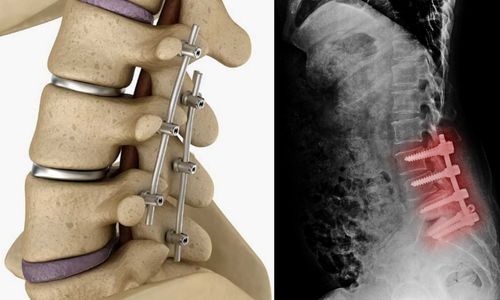

TRATAMENTOS E PROCEDIMENTOS

Cirurgia de Crânio e Coluna